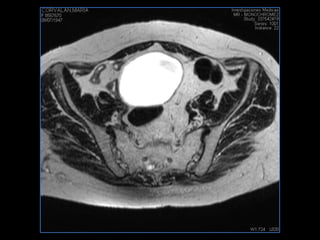

PROTOCOLO pelvis SAG T2, Y FAT SAT (FINOS) AXIAL T1  AX FAT SAT CON   GADOLINIO :  AX T1 Y COR T1 SAT: NO  FASE: RL THK: 3MM  COIL:  GAP: (FACTOR 1.4) 1MM FOV: 40 CM NEX:2 SINCRONIZACION RESPIRATORIA EN 3 O 4 CICLOS ALE

resonancia de abdomen